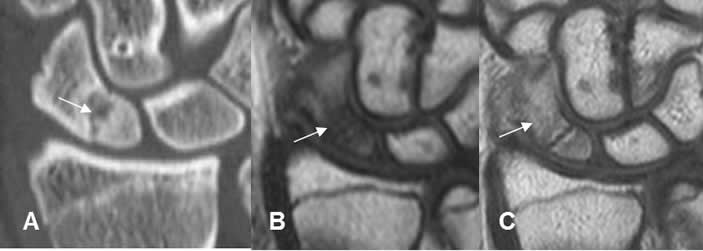

Fig 125. Seudoartrosis.

A: Rx AP y B: TAC reconstrucción sagital. Fractura con extremos escleróticos y con poca formación de callo óseo, por seudoartrosis.